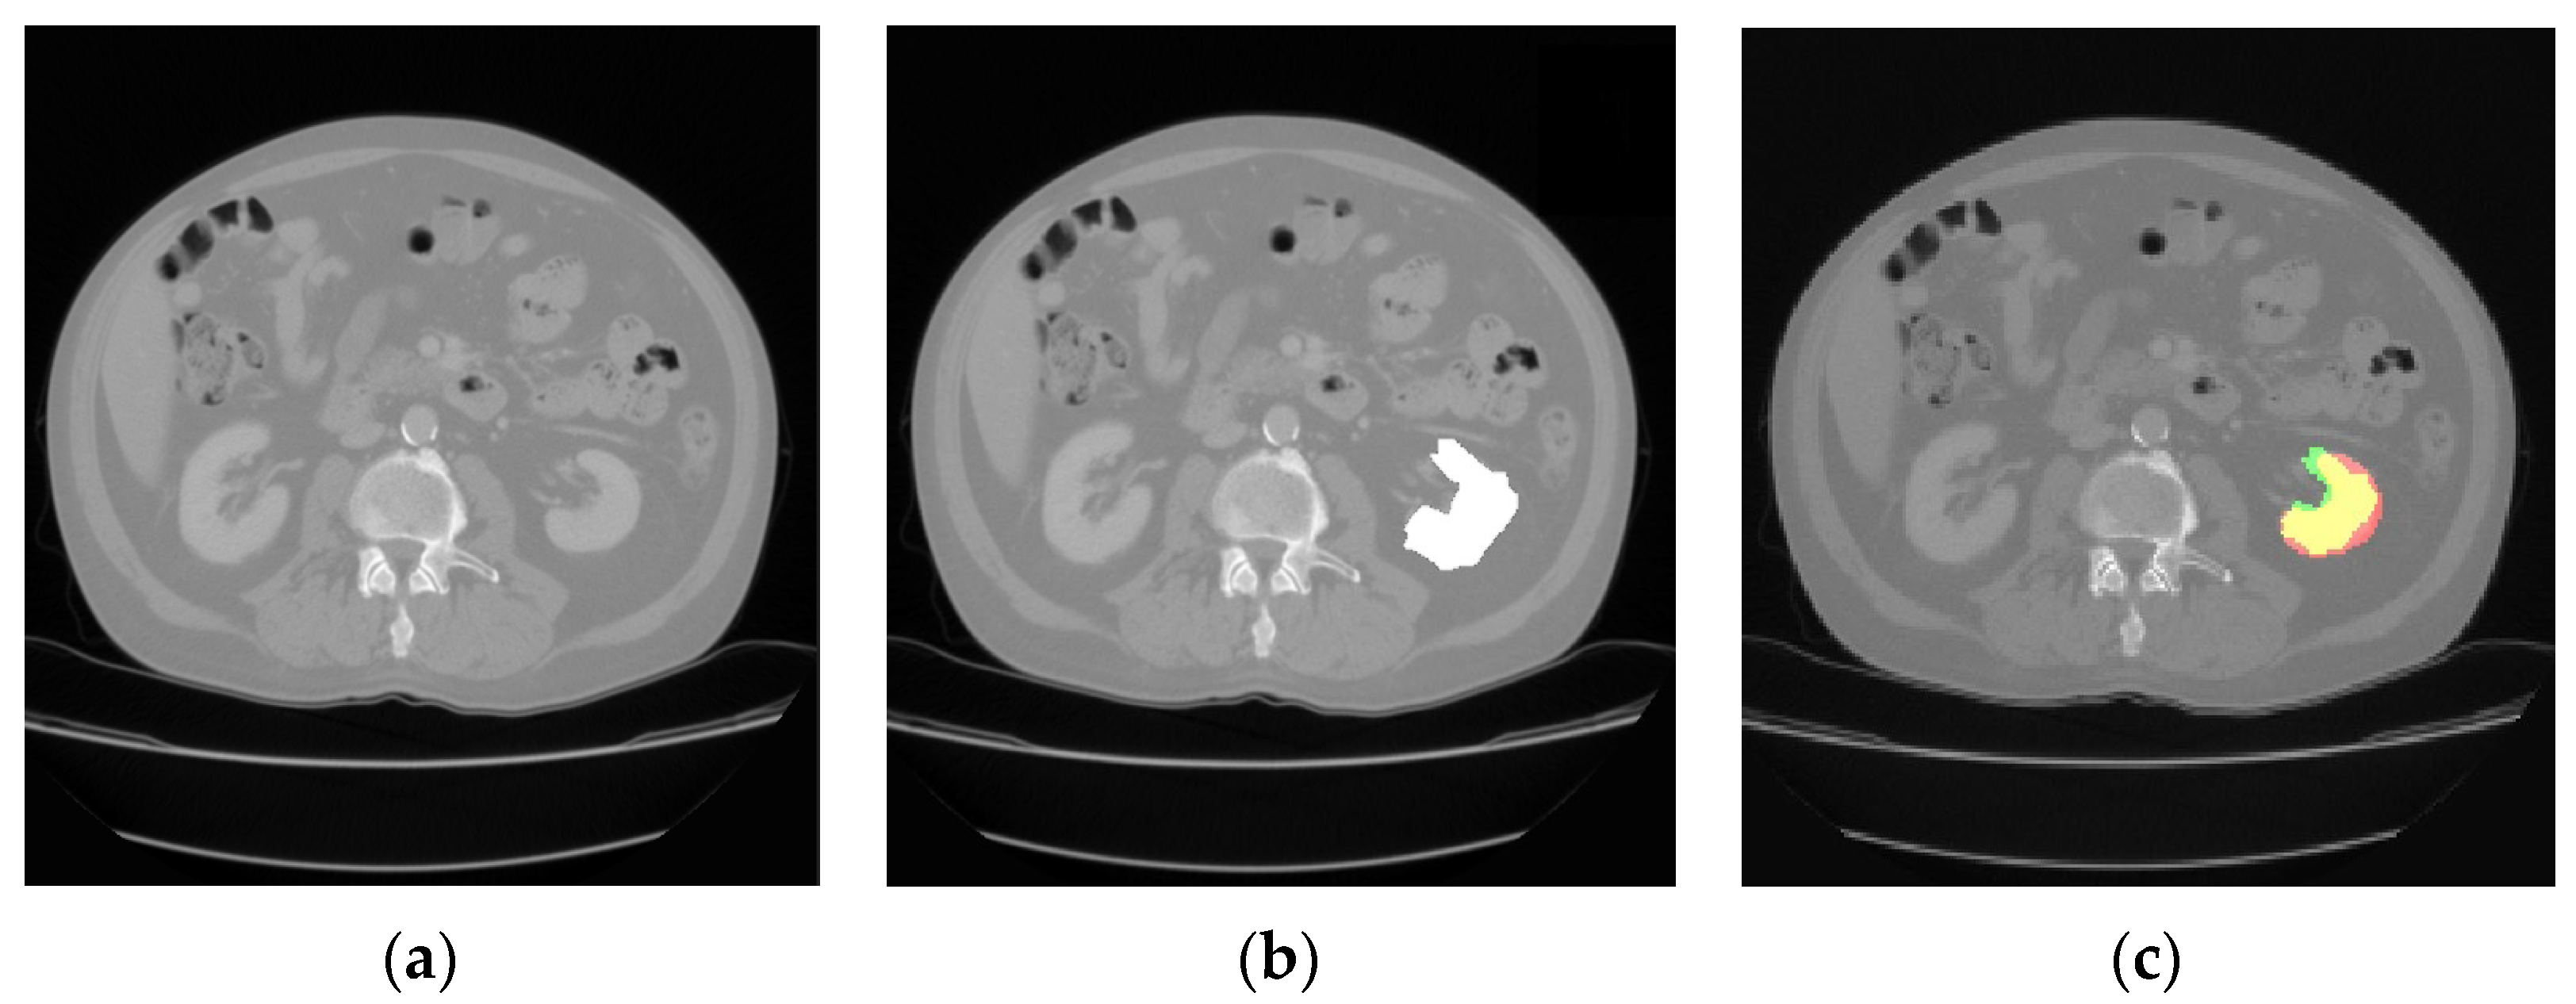

The comparison of the output results of the segmentation network and the expert segmentation of a healthy kidney is shown in Figure 3, while for the pathological kidney (renal tumor), the comparison of the output results of the segmentation network and the expert segmentation of a healthy kidney is shown in Figure 4. Regarding the potential bias of the medical experts, although it cannot be eliminated, we have striven to greatly reduce this bias by triple checking the segmentation of the area of interest. Therefore, a radiology resident (V.O.B.), a radiology fellow (G.M.C.), and a radiology attending physician (C.M.), with a combined 25 years of experience imaging renal cell carcinoma, utilized 3D Slicer [29] to manually segment the dataset. Concerning the color scheme utilized below, the red area represents the prediction, the green area the ground truth. The yellow area, therefore, represents the correctly predicted pixels.

Figure 3. CT image of a healthy kidney (a); the medical expert segmentation (shown in white) (b); and the result of the model’s prediction (c).